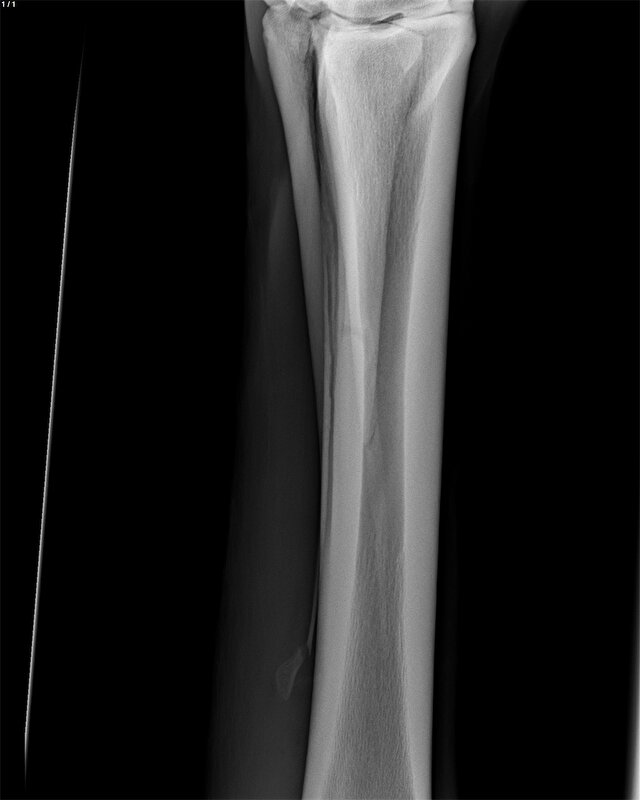

Icecrystal schreef:Mijn paard had precies dezelfde breuk als op jouw foto. Been bleef maar dik, verder niet kreupel.

Ik heb haar in Utrecht laten opereren voor rond de €1000,- . Een week boxrust en daarna de wei op. Na 2 weken wei was alles mooi slank en zijn we weer gaan opbouwen!

[ [url=m/uxbEy6.jpg]Afbeelding[/url] ]